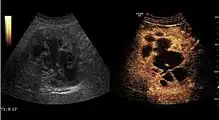

The ultrasound appearance is a well defined lesion, with very thin, almost unapparent walls, without circulatory signal at Doppler or CEUS investigation. The content is transonic suggesting fluid composition. The presence of membranes, abundant sediment or cysts inside is suggestive for parasitic, hydatid nature. Posterior from the lesion the acoustic enhancement phenomenon is seen, which strengthens the suspicion of fluid mass. They typically displace normal liver vessels but no vascular or biliary invasion occurs.

Liver cyst

Hydatid liver cyst. Diagnostic criteria are the presence of membranes and sediment inside.